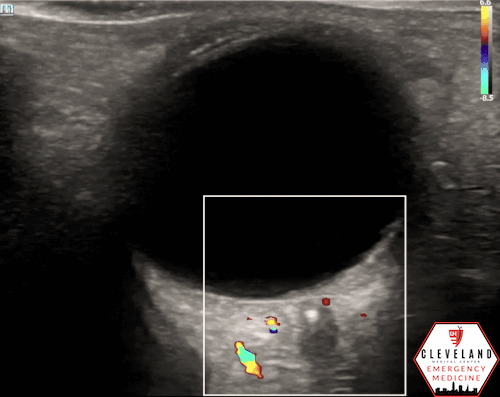

A hyperechoic focus over the distal optic nerve — referred to as the retrobulbar spot sign — has been observed on ocular ultrasound in cases of CRAO and may help differentiate it from other causes of painless monocular vision loss (7,8). Illustrated in Figures 4-6, this finding is considered highly specific for embolic CRAO and, when present, is associated with a significantly lower likelihood of temporal arteritis (9). However, its true prevalence remains unclear, and most studies evaluating its diagnostic accuracy have been small. In one study, the retrobulbar spot sign demonstrated a sensitivity of 83% and specificity of 100% for CRAO (9).

If a hyperechoic spot is identified, consider using color Doppler to assess for diminished or absent arterial flow distal to the focus (see Figure 6). Keep in mind that Doppler signal is angle-dependent, and poor probe positioning may limit its reliability.

Figure 5. Retrobulbar hyperechoic spot sign from our patient’s case

Figure 6. Color doppler shows lack of arterial flow over the optic nerve